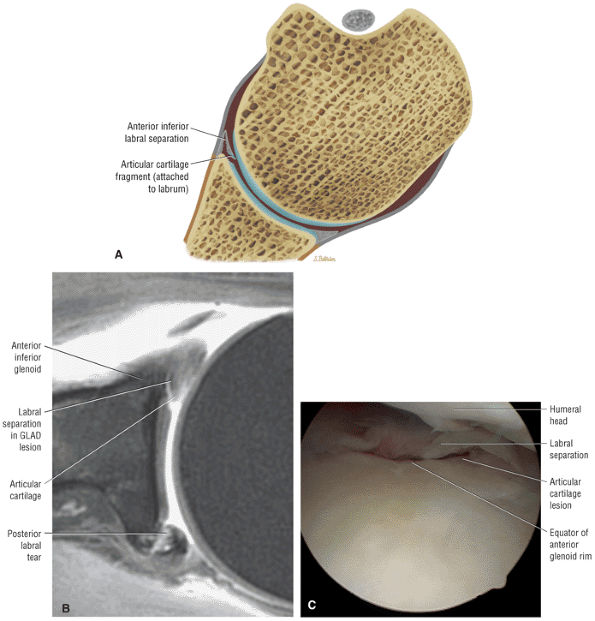

-

Primary extrinsic impingement is associated with abrasion of the rotator cuff against the inferior surface of the acromion.

Subacromial keel spurs are located on the anteroinferior lateral portion of the acromion.

Acromial thickness is important in planning subacromial decompression procedures.

The AC joint may hypertrophy, but it is not responsible for true impingement.